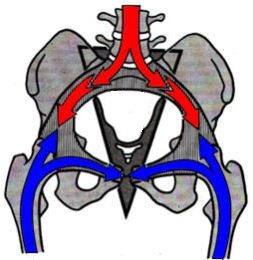

Tutta la colonna (sacro compreso) è implicata e fa parte di una fisiologia cha si sviluppa in senso discendente, mentre gli arti inferiori e il resto del bacino (anche comprese) appartiene ad una  fisiologia che si sviluppa in senso ascendente.

Quando il sacro e la colonna sono relativamente fermi e gli arti inferiori in movimento, oppure quando sono fermi gli arti inferiori e il bacino mentre la colonna è in movimento, si realizza sempre un movimento a livello dell’articolazione Ileosacrale (tra sacro e quella porzione del bacino chiamata ileo). Le lesioni e i disturbi a livello dell’ileo sono sempre riferite all’articolazione sacroiliaca, esso infatti risponde a forze discendenti (gravità) e ascendenti (risposta del suolo), e qui inoltre le due forze si incrociano.

Le sacroiliache non sono articolazioni di movimento ma di ammortizzamento, non vengono mobilizzate da muscoli e il loro sistema legamentoso riceve il peso di gravità e rappresentano un sistema di scivolamento, di adattamento e di guida del movimento.

Quindi bisogna ricercare che cosa sta provocando una disfunzione a livello sacro-iliaco, considerando sia una possibilità discendente, sia ascendente!